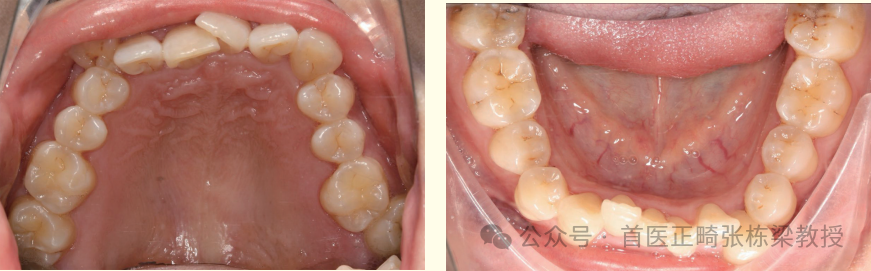

我们使用上下颌种植支抗,远中直立后牙获得间隙,配合必要的片切获得间隙排齐前牙。

但是需要时间,这位女士的牙齿问题解除时间是两年,因此牙齿矫正中需要正畸医生的信心和患者的耐心。